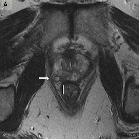

Neurofibromas are benign peripheral nerve sheath tumors usually solitary and sporadic, however, there is a strong association with neurofibromatosis type 1 (NF1). These tumors present as a well-defined hypodense mass with minimal or no contrast enhancement on CT. On MRI, they usually are T1 hypointense and T2 hyperintense with heterogeneous contrast enhancement.

MRI

- T1: hypointense

- T2

- hyperintense

- target sign

- a hyperintense rim and central area of a low signal may be seen

- this is thought to be due to a dense central area of collagenous stroma

- although this sign is highly suggestive of neurofibroma, it is occasionally also seen in schwannomas and malignant peripheral nerve sheath tumors

- fascicular sign

- T1 C+ (Gd): heterogeneous enhancement